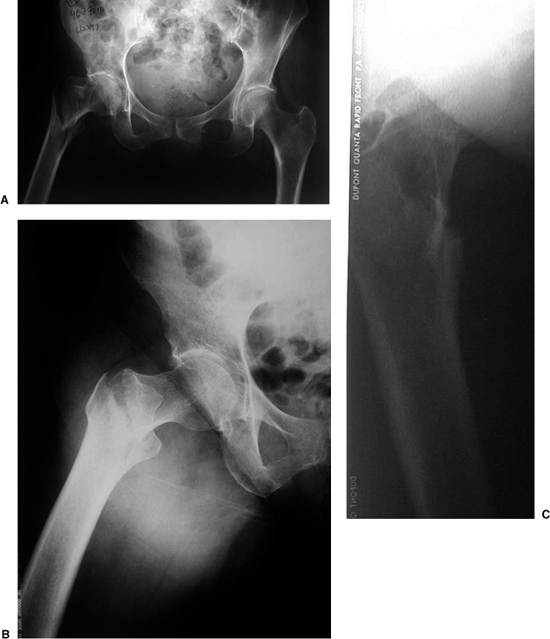

suspected hip fractures include an anteroposterior (AP) view of the

pelvis, and an AP and cross-table lateral of the injured proximal femur

(Fig. 16.2). A cross-table lateral radiograph

is necessary to evaluate the posteromedial cortex for signs of

comminution. In situations where the fracture geometry is not clear due

to deformity, an AP view of the hip internally rotated 15 to 20 degrees

may be helpful (Fig. 16.3). An AP view of the

contralateral side is helpful, particularly as a means of assessing the

size and angle of the implant for intramedullary fixation.

![]() |

Figure 16.2. A. AP view of the pelvis. B. An AP and (C) cross-table lateral view of the hip revealing a right intertrochanteric fracture.